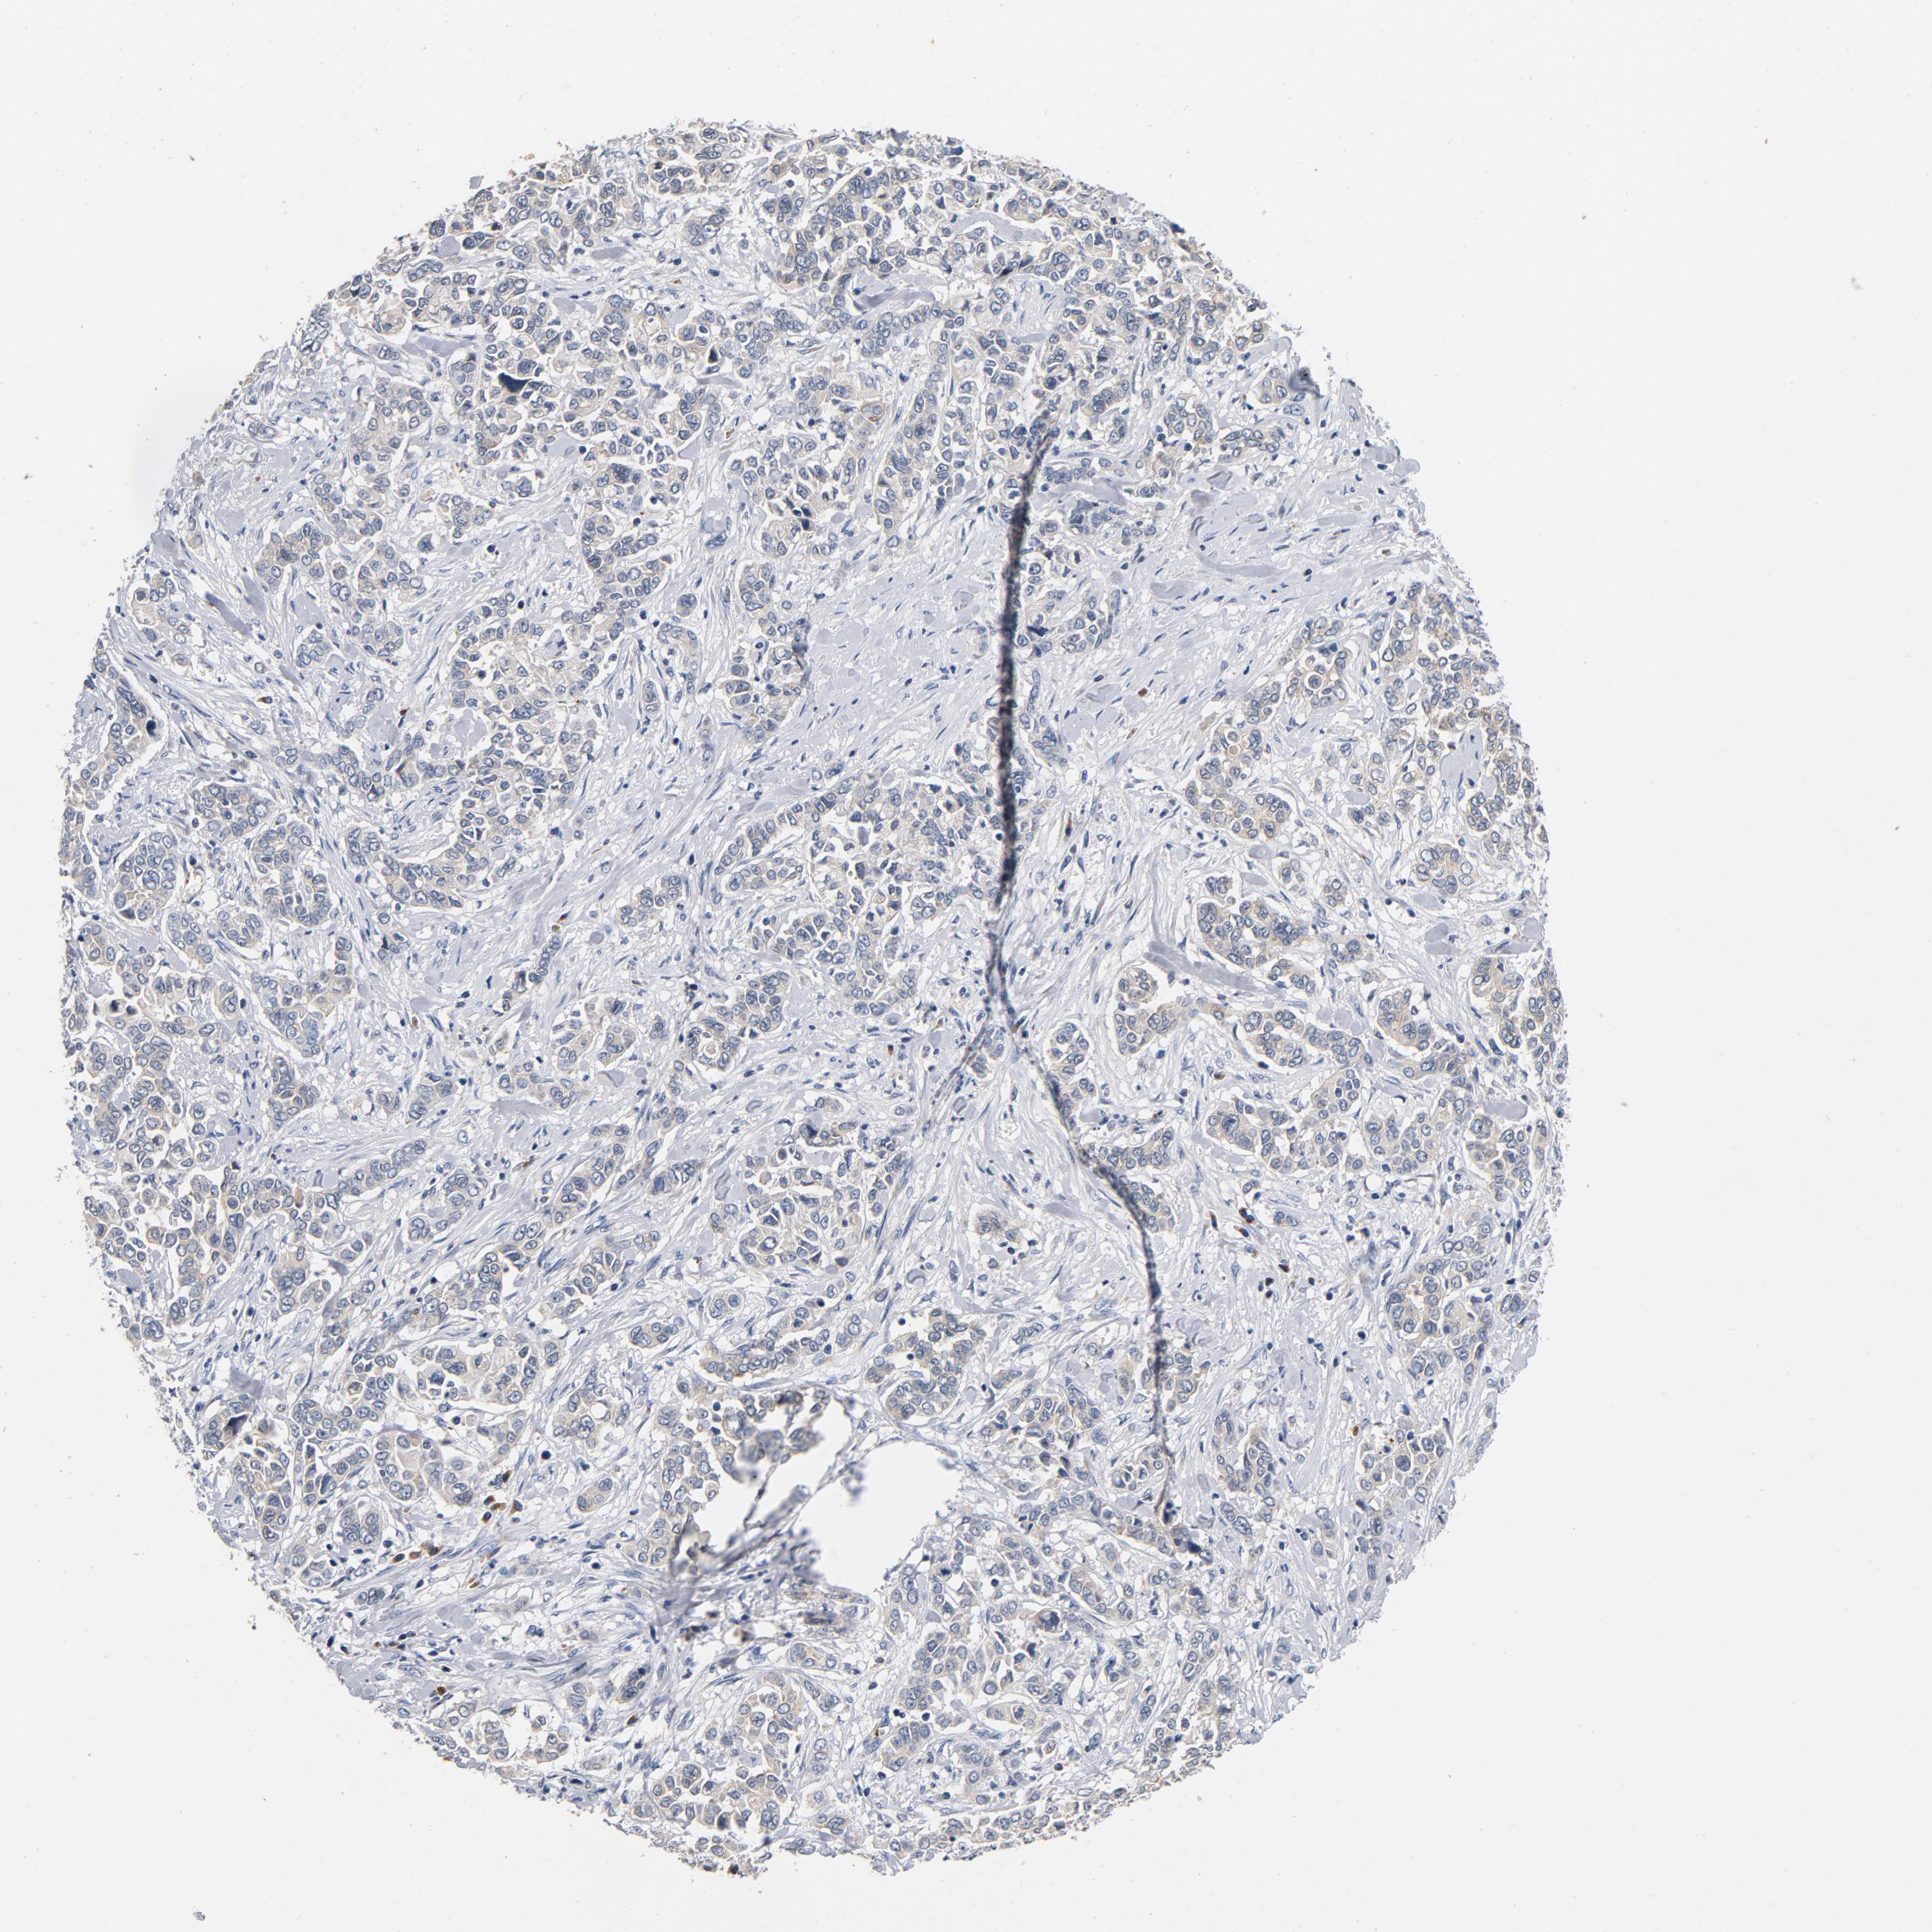

PANCREATIC CANCER - Protein expressioni

A mouse-over function shows sample information and annotation data. Click on an image to view it in a full screen mode. Samples can be filtered based on level of antibody staining by selecting one or several of the following categories: high, medium, low and not detected. The assay and annotation is described here.

Note that samples used for immunohistochemistry by the Human Protein Atlas do not correspond to samples in the TCGA dataset.

Antibody stainingi

Antibody staining in the annotated cell types in the current human tissue is reported as not detected, low, medium, or high, based on conventional immunohistochemistry profiling in selected tissues. This score is based on the combination of the staining intensity and fraction of stained cells.

Each image is clickable and will lead to virtual microscopy that enables deeper exploration of all samples and also displays staining intensity scores, fraction scores and subcellular localization as well as patient and tissue information for each sample.

Antibody HPA003927

Staining

High

Medium

Low

Not detected

Intensity

Strong

Moderate

Weak

Negative

Quantity

>75%

75%-25%

<25%

None

Location

Nuclear

Cytoplasmic/membranous

Cytoplasmic/membranous,nuclear

Adenocarcinoma, NOS